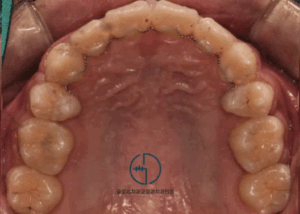

방치하면 주걱턱 될 수 있습니다. 중랑구 교정치과 어린이 반대교합 에 사용되는 2×4 장치

안녕하세요 중랑구 교정치과 김정은 원장입니다. ^^ "우리 아이 아랫니가 윗니보다 더 앞에 나와 있어요." 성장기 자녀를 둔 부모님들께서 흔히 우려하는 문제 중 하나입니다. 이는 단순히 심미적인 문제를 넘어, 아이의 턱…